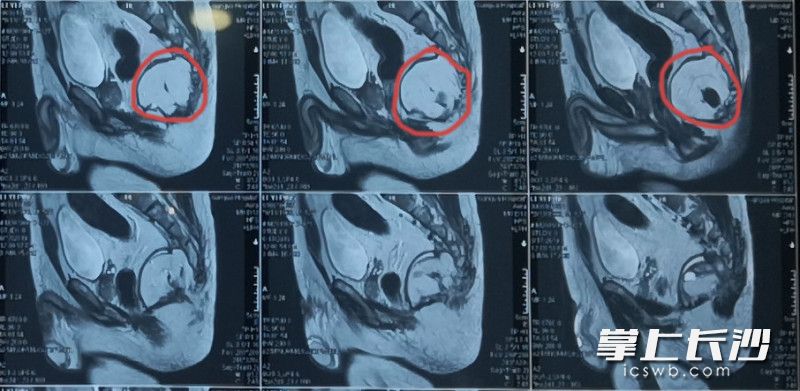

患者术前的核磁共振检查片

该科副主任医师莫黎全面细致地为李先生做了检查,最终被确诊为骶前囊肿。之前多次手术未能痊愈的关键,是未能完整切除囊壁组织,且反复手术导致周围组织粘连明显。核磁共振MRI检查结果显示,肿瘤较大,位置向上到达骶骨中段,后方及上方与骶前组织粘连明显,前面与直肠后壁紧密相贴。手术风险和难度都很高,不但要切除尾骨,还要切除部分骶骨,容易导致大出血,也可能损伤直肠而不得不做造瘘手术。